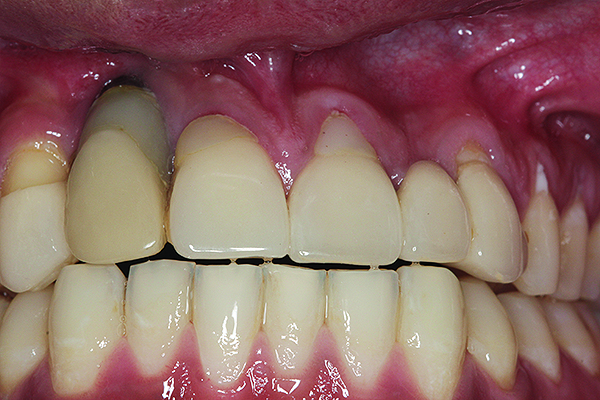

The implant of the patient shown in Figure 8 demonstrated all three of the red flag situations: it was placed too far buccally, had inadequate bone and soft tissue at the time of implant placement, and lost bone and soft tissue post implant placement. Correcting this required increased time, cost, and surgeries (Figure 9).

A implant restoration with a buccal dehiscence of bone and soft tissue caused by poor implant positioning, lack of keratinized tissue prior to implant placement, and soft tissue recession post implant restoration.

Figure 8

The same implant in Fig 8, 7 years following treatment, which included two autogenous connective tissue grafts and a bone augmentation surgery with a combined allograft and xenograft mixed with two biologics.

Figure 9